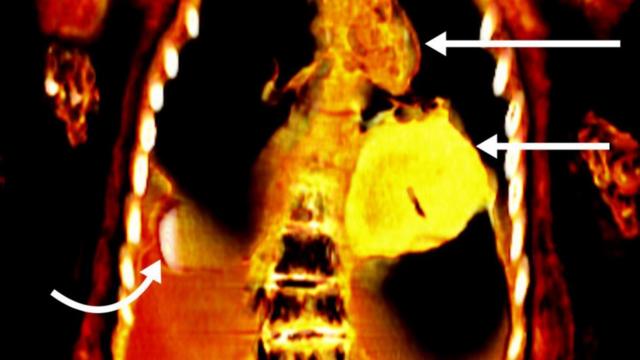

Imagempoker dinheiro real gratistomografia mostra o coraçãopoker dinheiro real gratisouro da múmia

As imagens mostraram que sob as mortalhas que cobriam o corpo do jovem havia um objeto ao lado do pênis, uma língua dourada dentro da boca e um objetopoker dinheiro real gratisformapoker dinheiro real gratiscoração, também feitopoker dinheiro real gratisouro, abaixo da cavidade torácica.